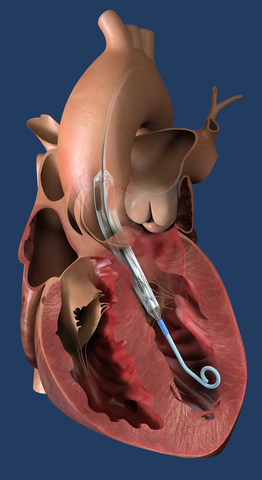

Impella ECP, the world's smallest heart pump, is placed percutaneously into the heart's left ventricle. (Graphic: Business Wire)

Impella ECP is the world’s smallest heart pump and the only heart pump compatible with small bore access and closure techniques. It is 9 Fr in diameter upon insertion and removal from the body. Once in the body, it expands and supports the heart’s pumping function, providing peak flows up to 5 L/min.

Both patients enrolled in the trial received Impella ECP support during challenging left main coronary bifurcation stent procedures involving heavily calcified lesions. After Impella ECP was removed, the first patient was closed with an 8 Fr closure device.